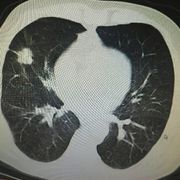

胸片怎么看

学会看胸片是临床医生必备的技能之一,首先,看胸壁的X线表现,观察胸壁软组织有大的肿块,有皮下积液、积气,同时观察肋骨的连续性是否有中断,这是肋骨骨折的X线征象...73227人收听

在临床上胸部X光片检查是常用的一种检查方法,它是利用X线产生图像,从而观察胸部的病变。胸片的观察需要按一定的顺序,一般可以按照从上往下的顺序,观察双肺上叶...1人收听